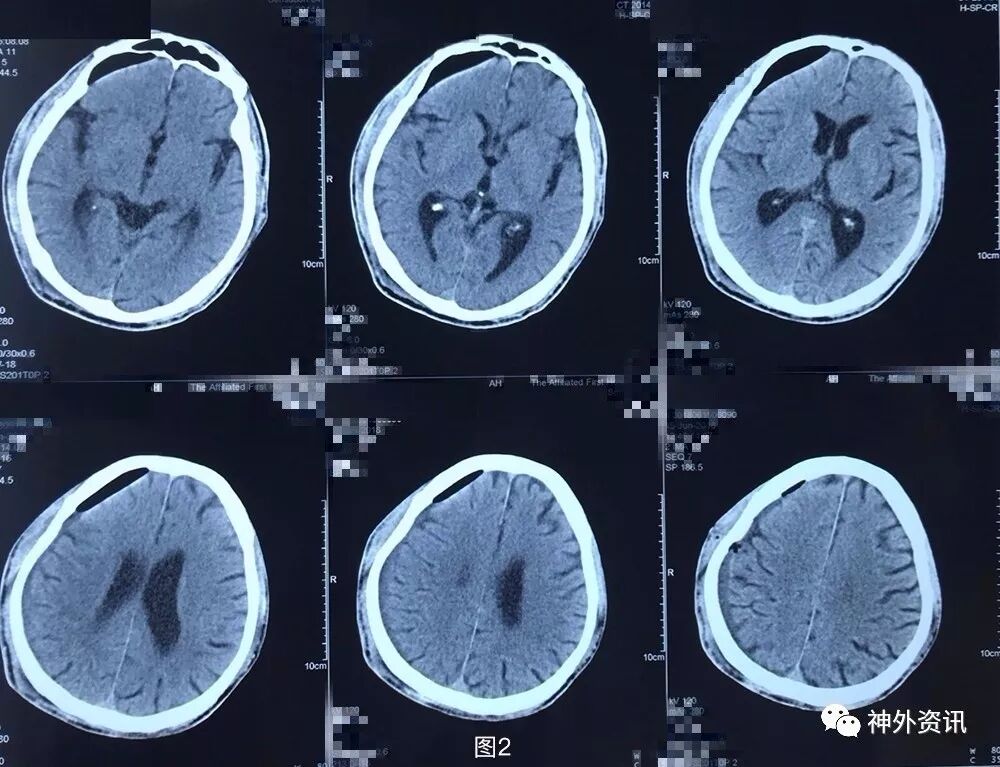

患者5月前不慎头部外伤,当时无黑懵晕厥,无头痛头晕,未重视治疗,3月余前无明显诱因下出现头痛,伴头晕,伴行走不稳,前往外院就诊,查头颅CT示:右侧额颞顶枕部慢性硬膜下血肿考虑(图1),行钻孔引流术。术后复查头颅CT提示右侧额颞顶枕慢性硬膜下血肿钻孔引流术后改变(图2),术后症状好转出院。2月前(术后1月)患者再次出现头痛晕头晕等症状,复查头颅CT:右侧额颞顶枕硬膜下血肿,脑实质受压,中线轻度左偏(图3)。遂再次行右额颞顶枕部硬膜下血肿钻孔引流术,术后患者头痛无明显好转,伴左侧肢体乏力,复查头颅CT见术后局部血肿形成(图4)并进行性增大(图5)。

图2. 外院第1次术后头颅CT提示:右侧额颞顶枕慢性硬膜下血肿钻孔引流术后,血肿基本清除。